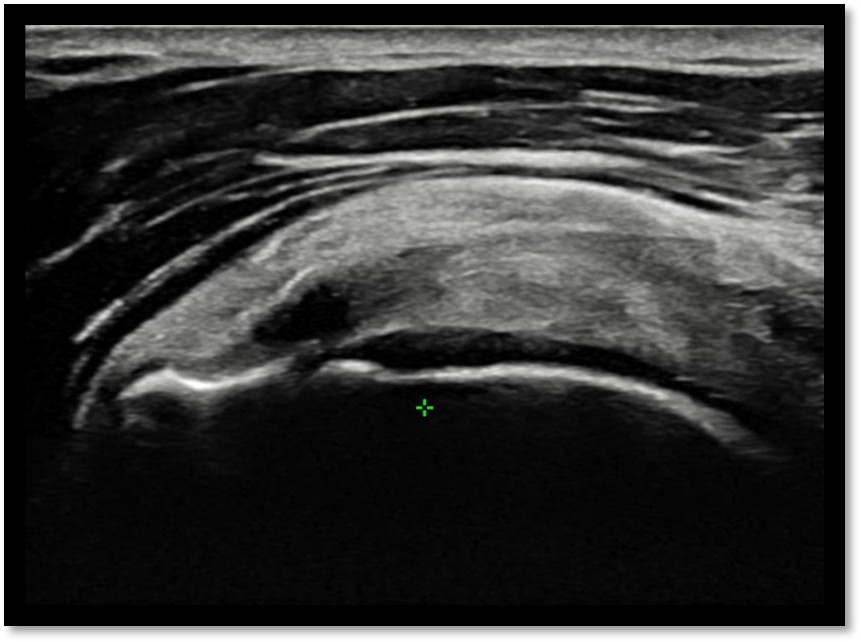

MRI와 초음파를 다시 검토했습니다.

회전근개 극상건의 관절면측(articular-side) 부분파열.

Step 2: 초음파 유도 하 가이드 삽입

초음파로 파열 부위를 실시간 확인하면서 특수 가이드를 삽입합니다.